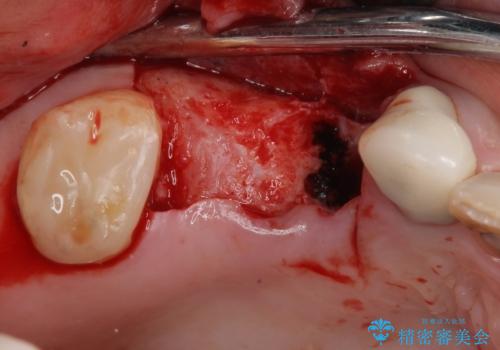

- 欠損や破折により失われた奥歯に、インプラント治療を希望して来院された患者様です。

欠損部はすぐにインプラント埋入が可能で、手前の歯根が残存している部位も、できれば抜歯をして奥と一緒に埋入をしたいところでしたが、破折による炎症が大きいため、2回に分けてインプラント埋入を行うこととしました。